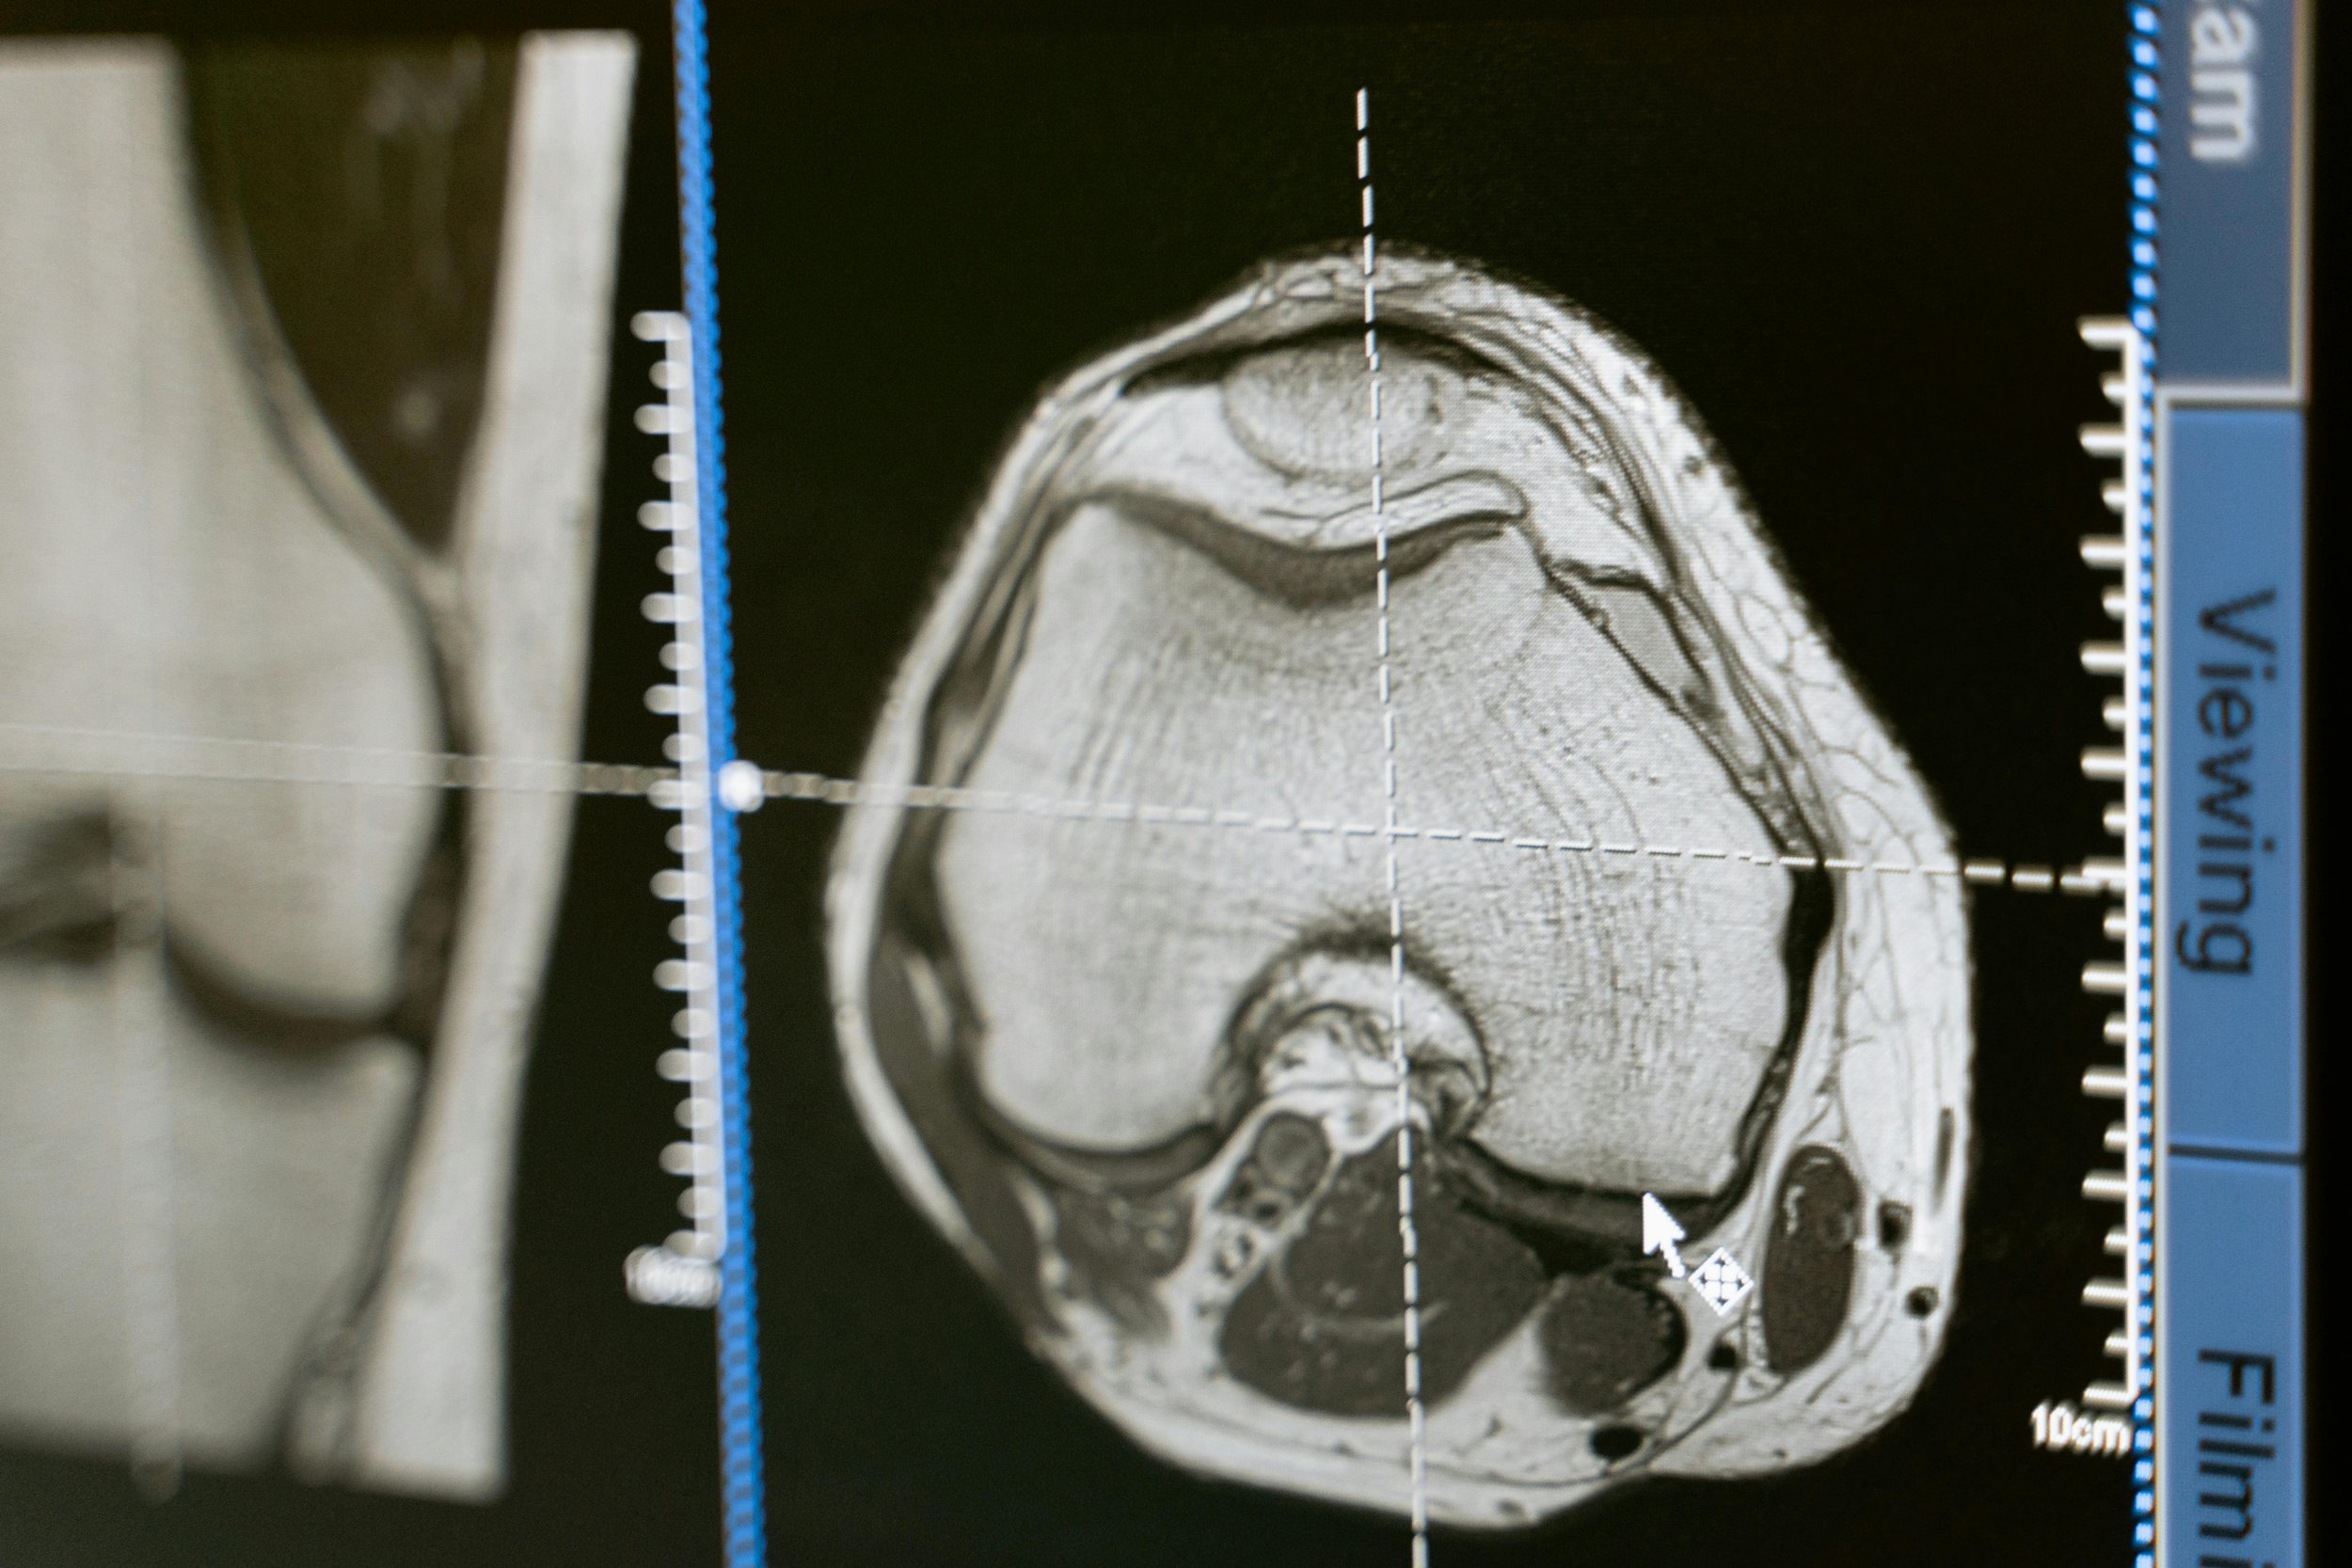

El diagnóstico se realiza mediante exploración física, historia clínica y estudios de imagen cuando son necesarios. La resonancia magnética puede ayudar a identificar el tipo y localización de la lesión, pero la decisión de tratamiento debe basarse también en los síntomas y la exploración.